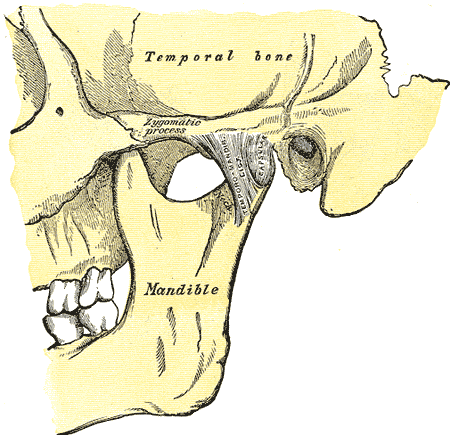

Fortunately, I was at a chiropractic college and could receive treatment for TMJ (temporomandibular joint) injury. I became intensely committed to learn everything I could about the TMJ and everything related to jaw problems.

After almost 10 years I have had the opportunity to help many patients with jaw pain and associated problems such as ear pain, sinus troubles, neck pain, headaches, vertigo and dizziness. These conditions are often related to each other and you may experience one or all of them.